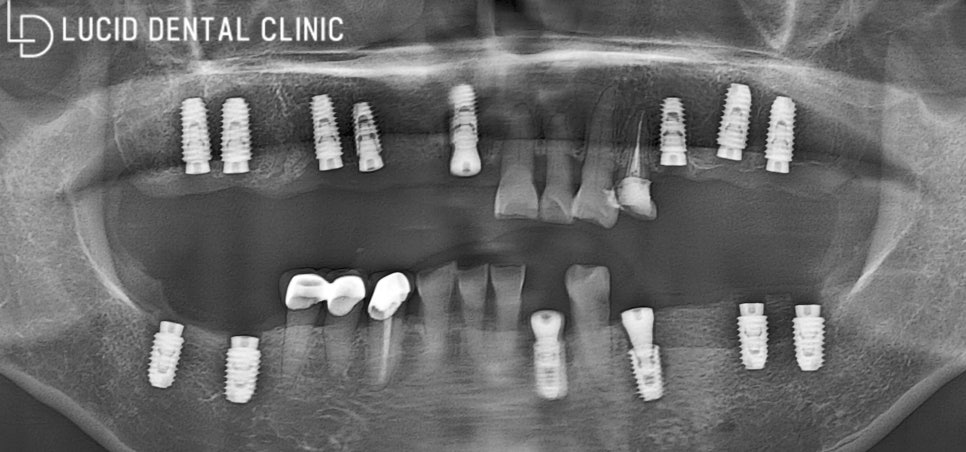

플라즈마 활성화를 이용하여

픽스처(Fixture) 즉시 식립을 진행했어요.

픽스처 식립하고 나서

나중에 보철을 올릴 때

픽스처와 잘 연결될 수 있도록

어버트먼트를 체결하였습니다.

이제 치은과 치조골이 잘 회복될 수 있도록

잠시 기다리는 시간을 가질 겁니다.

평균적으로 상악은 보통 3~4개월,

하악은 2~4개월 정도 걸리는 편인데요.

저와 꾸준한 관리를 병행하면서

함께 기다리기로 약속했습니다 :)